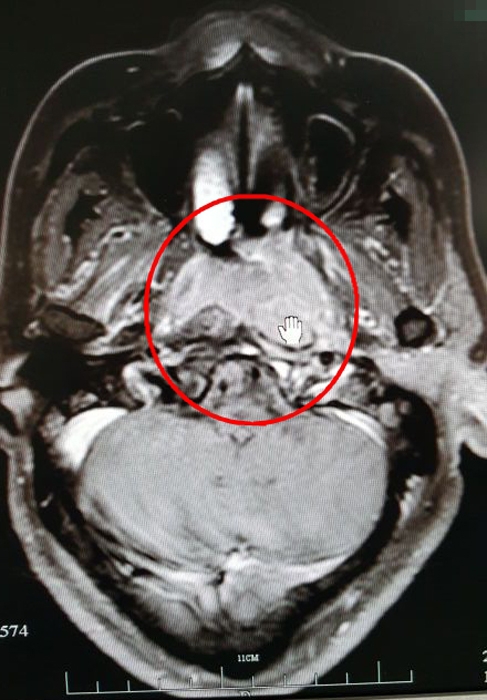

??? 2015年7月,放療科為吳大姐進行了同步放化療,此后,進行了兩次全身化療。

放療前的CT影像(紅圈處為病灶)